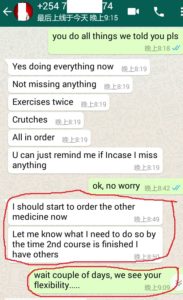

1. The Gentleman in Kenya started his treatment at his home April 27, now he said: (will update his more progresses soon)

3. The gentleman in India just started May, 2019. Actually he started on April 28, 2019 but he used it in wrong way and got less effects, ONLY on May 8, 2019 during our follow-up, we found his wrong-doing, and then corrected him. ONLY in 2 days, his pains significantly reduced!!!!